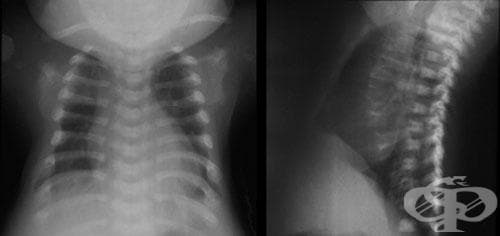

Медицина и диагностика: Аномалии ребер на рентгене